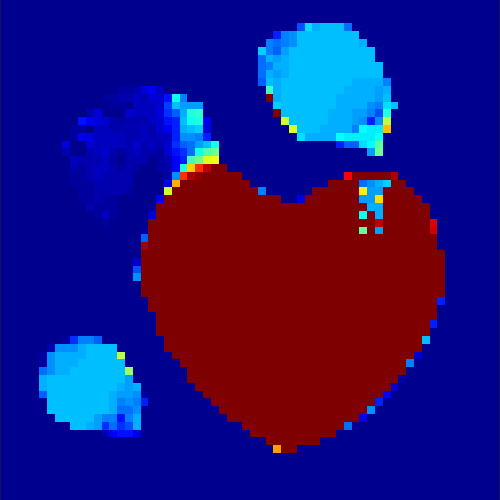

The first data set consists of a heart-shaped region and three circles on a static background (see figure 1 (a)). The two smaller circles are assumed to belong to

the same tissue type and therefore to the same subregion, which causes a total of four subregions, including the background. To simulate a more realistic application of dynamic SPECT

imaging, we used a synthesized representation of a rat liver as a second data set (see figure 1 (b)). The temporal concentration curves used to simulate the data sets

are shown in figure 2. As before, the total number of subregions was chosen to be equal to four in order to provide a both simple and realistic shape model.

In a first test, every image sequence was reconstructed out of the exact given sinograms. Additionally we tested noise corrupted data by first scaling the sinogram by a parameter , corrupting them with Poisson noise via the MATLAB imaging toolbox command imnoise and finally rescaling the image to the original range (see figure 4). The average count number per time step (i.e. the average of the discrete -norm of the data at each time step) is approximately in case of the heart-shaped data set and ca. in case of the rat liver simulation. The results at a certain number of time steps can be seen in figure 6 and 7. For comparison, we additionally performed a reconstruction with a simple alternating EM method, keeping the assumption that the tracer can be modelled as a sum of indicator functions and subconcentration curves, but neglecting any regularization terms. In all tests, the outer iteration number was set to 1000 with 10000 inner iterations per subproblem, to obtain a result within a reasonable time period. As stopping criterion, we chose the primal dual residual (cp. [12]) for the inner and the maximum over the Frobenius norms of and for the outer iterations. The results are displayed in 6 and 7 respectively.

As one can see in both figures, the reconstruction method applied to each data set performs very well, especially in contrast to the simple alternating EM method. This clearly shows the benefits of the proposed regularization methods. In case of noise-free given data, the shape of every object, where especially the heart is of higher interest, is clearly defined. As expected, we often observe errors in the edges of each region and where two regions are directly connected (the heart and the upper left circle). This causes the algorithm to incorrectly assign these pixels to another region. Furthermore, the reconstruction difficulties increase with an increase in noise. Some more pixels are assigned to the wrong region, which leads to a small hole-like structure within the heart region and causes a slight blurring effect. In the second data set the method clearly outperforms several other approaches by providing very clearly defined regions and even reconstructing fine structures of the phantom. However, as mentioned before, a clear reconstruction of the rat liver required highly optimized parameter sets, which makes the whole problem quite susceptible to parameter changes.